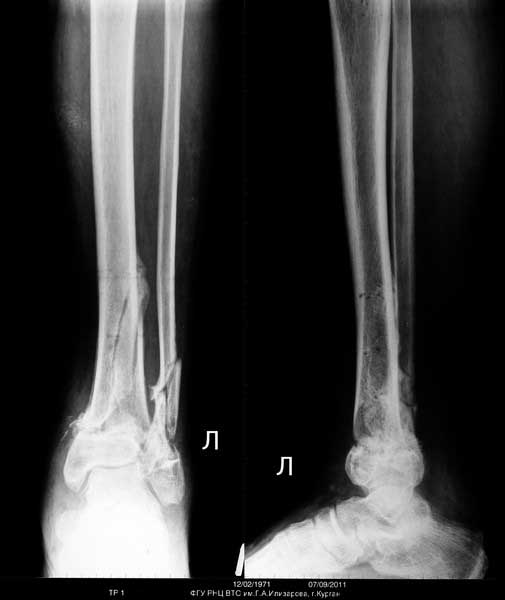

Уважаемый Сергей,

Я бы порекомендовал, если кожные покровы голени позволяют- произвести остеосинтез пластинами через общий передне-наружный доступ. И в первую очередь зафиксировать полутрубчатой 4,5мм или компрессионной 3,5мм пластиной АО перелом н/3 малоберцовой кости, чтобы стабилизировать отломки б/берцовой по длине.

Если с кожей не то- попытаться получить репозицию под ЭОП-ом и наложить аппарат АО до голеностопного сустава (собирать Илизаров - долго, нудно, да и, наверное нет необходимости...)

Уважаемый Сергей! Следует уточнить(для уважаемого сообщества) , что переломы находятся на разных конечностях, поэтому восстановление длины бедра потребует равнозначной коррекции длины голени. Либо, как предлагает профессор Djoldas Kuldjanov, не добиваться полной репозиции и пожертвовать частью дистального отломка, сохранив ось и ротацию. Корригировать длину голени проще ввиду меньших усилий по преодолению ретракции мягких тканей. Хотя пациент молодой и желательно наиболее полно восстановить конечности. Несомненно,аппарат Илизарова собирать долго и нудно и неохота, но возможность управляемой фиксации при минимальных экономических затратах перевешивает данные "недостатки". Да и не располагаем АО фиксаторами, гексаподами. Следует учесть и то , что при одномоментной коррекции длины голени (3,5 - 4 см) могут возникнуть трудности с зашиванием и заживлением операционных доступов. Еще позволю уточнить, что клинических признаков консолидации на голени нет - подвижность полная, что не потребует остеотомии малоберцовой кости. Поэтому желаю Вам, Сергей, удачи в одномоментной коррекции деформации бедра и остеосинтезе, но нужно быть готовым к варианту Александра Николаевича - дистрактор, дозированная коррекция смещения по длине, остеосинтез.

Для оценки степени сращения костей голени рекомендуется сделать КТ срезы. И возможно, для голени не надо предпринимать ничего. Там процесс консолидации заканчивается, и хотя форма далека от идеала, но не так уж плоха. Уже время для нагрузки, и дайте возможности нагружать! Время покажет, и в зависимости от активности в дальнейшем можно обсудить план лечения в будущих дисскуссиях.